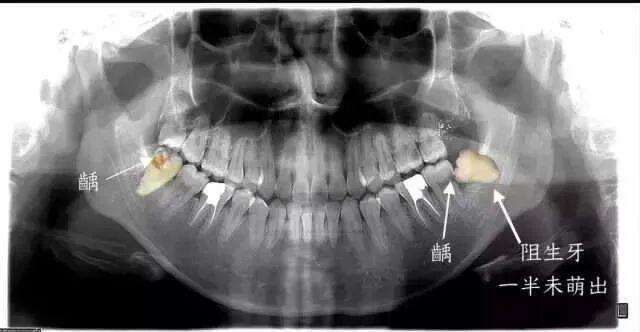

从下图可见,这些是被拔去的相对完整智齿,而更多的智齿其实已经在拔牙过程中四分五裂。即便如此,这些幸存下来的智齿,或多或少也已经出现了各种龋损和破坏。

长歪的智齿非常不容易清洁,食物常常会残留,有的就会导致智齿及周围组织疼痛;更严重的是,还会导致智齿前方的磨牙出现蛀牙,进一步则出现牙痛;最严重的、也非常常见的状况,智齿要拔掉先不说,连同智齿前方的第二磨牙都出现不可挽救的龋坏,只能一起拔掉。

▲ 智齿前方的牙齿已经出现了蛀洞,即龋病

医生同时表示,健康的智齿可以不拔,还有一些智齿深深埋在骨头里,而且完全没有萌出到口腔的迹象,那么也可以先不拔。但是要保持观察,一有动静,还是要防范!